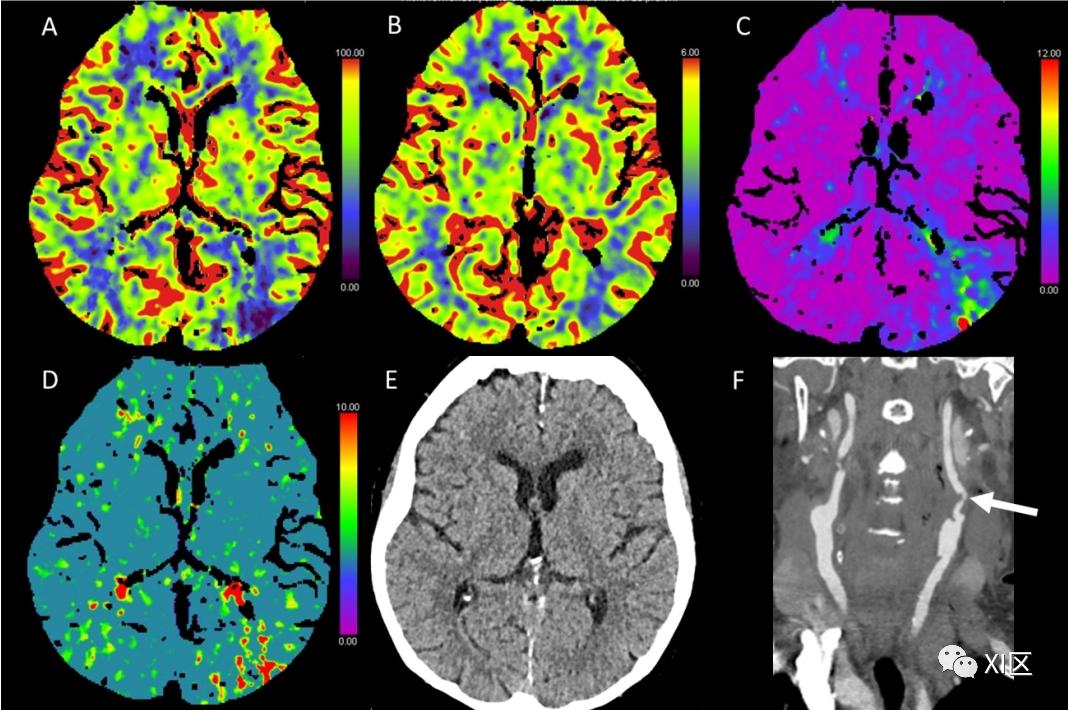

图1、图2、图3和图4给出了急性幕上卒中的例子。图5是一个恶性右侧MCA梗死的随访检查。

图1 脑部CTP产生的彩色编码图:(A)脑血流量量(CBF)[mL/100 g/min],(B)脑血容量(CBV)[mL/100 g],(C)Tmax [s],以及(D)平均通过时间(MTT)[s]。(E)CT平扫(NECT)和(F)动脉CT血管成像(CTA)。该患者接受了心导管检查,以关闭房间隔缺损。之后,该患者出现了左侧偏瘫。NECT显示灰白质分化略有减少。在右侧的大脑中动脉(MCA)区域,CBF和CBV降低,Tmax和MTT延长。CTA显示右侧颈内动脉远端闭塞。